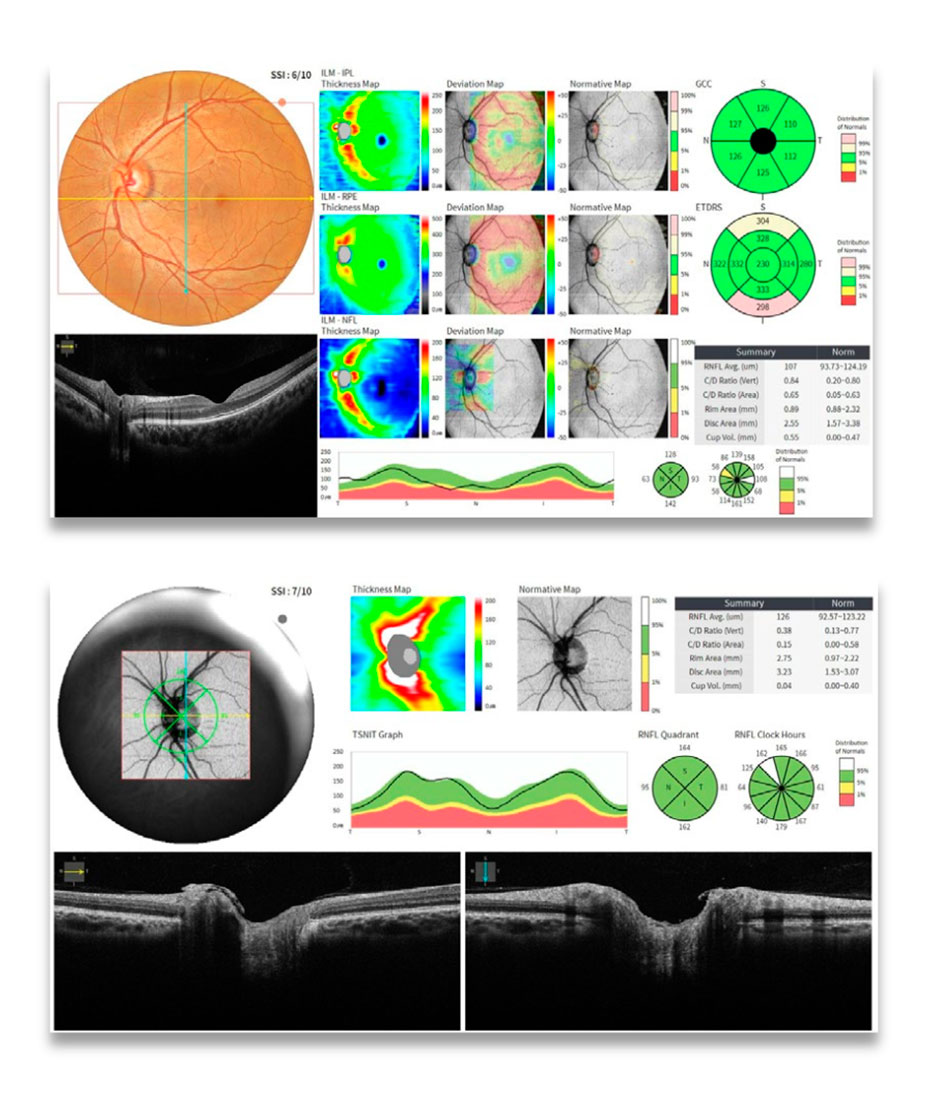

Avaliação detalhada da retina em casos de degenerações, edemas e descolamentos.

Diagnóstico e acompanhamento do glaucoma com análise de RNFL, células ganglionares e disco óptico.

Análise coroidal e vascular com Angio-OCT para detecção de neovascularizações e alterações microvasculares.

- Topografia: 16 mapas (curvaturas anterior e posterior)

- Análise Angio-OCT: FAZ, densidade vascular, progressão e comparação

- Software: Relatórios comparativos, base normativa, análise de progressão